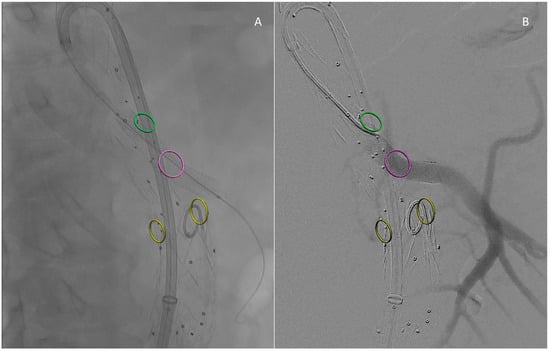

Figure 2. Intraoperative images: Result after bridging component deployment (A). Angiographic control (B). Circles mark the origin of reno–visceral vessels according to fusion guidance: green is for the Celiac Trunk, purple for the Superior Mesenteric Artery (the vessel just bridged), and yellow for the renal arteries.